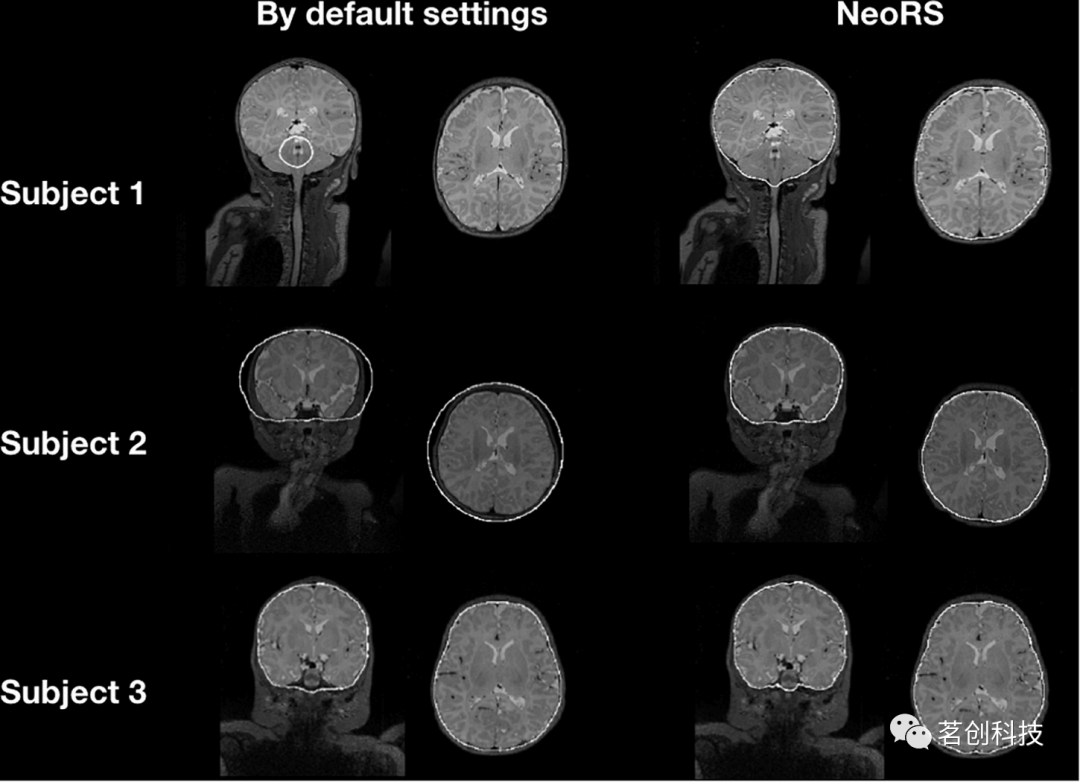

颅骨剥离

图5显示了新生儿的默认颅骨剥离与NeoRS颅骨剥离参数的比较情况。在默认设置下,可以观察到一些具有不同大脑大小的被试的颅骨剥离失败,相比之下,当使用NeoRS参数时,颅骨剥离对于所有处理过的被试仍然具有稳健的结果。

图5.比较默认bet2设置和优化的NeoRS设置的颅骨剥离参数。